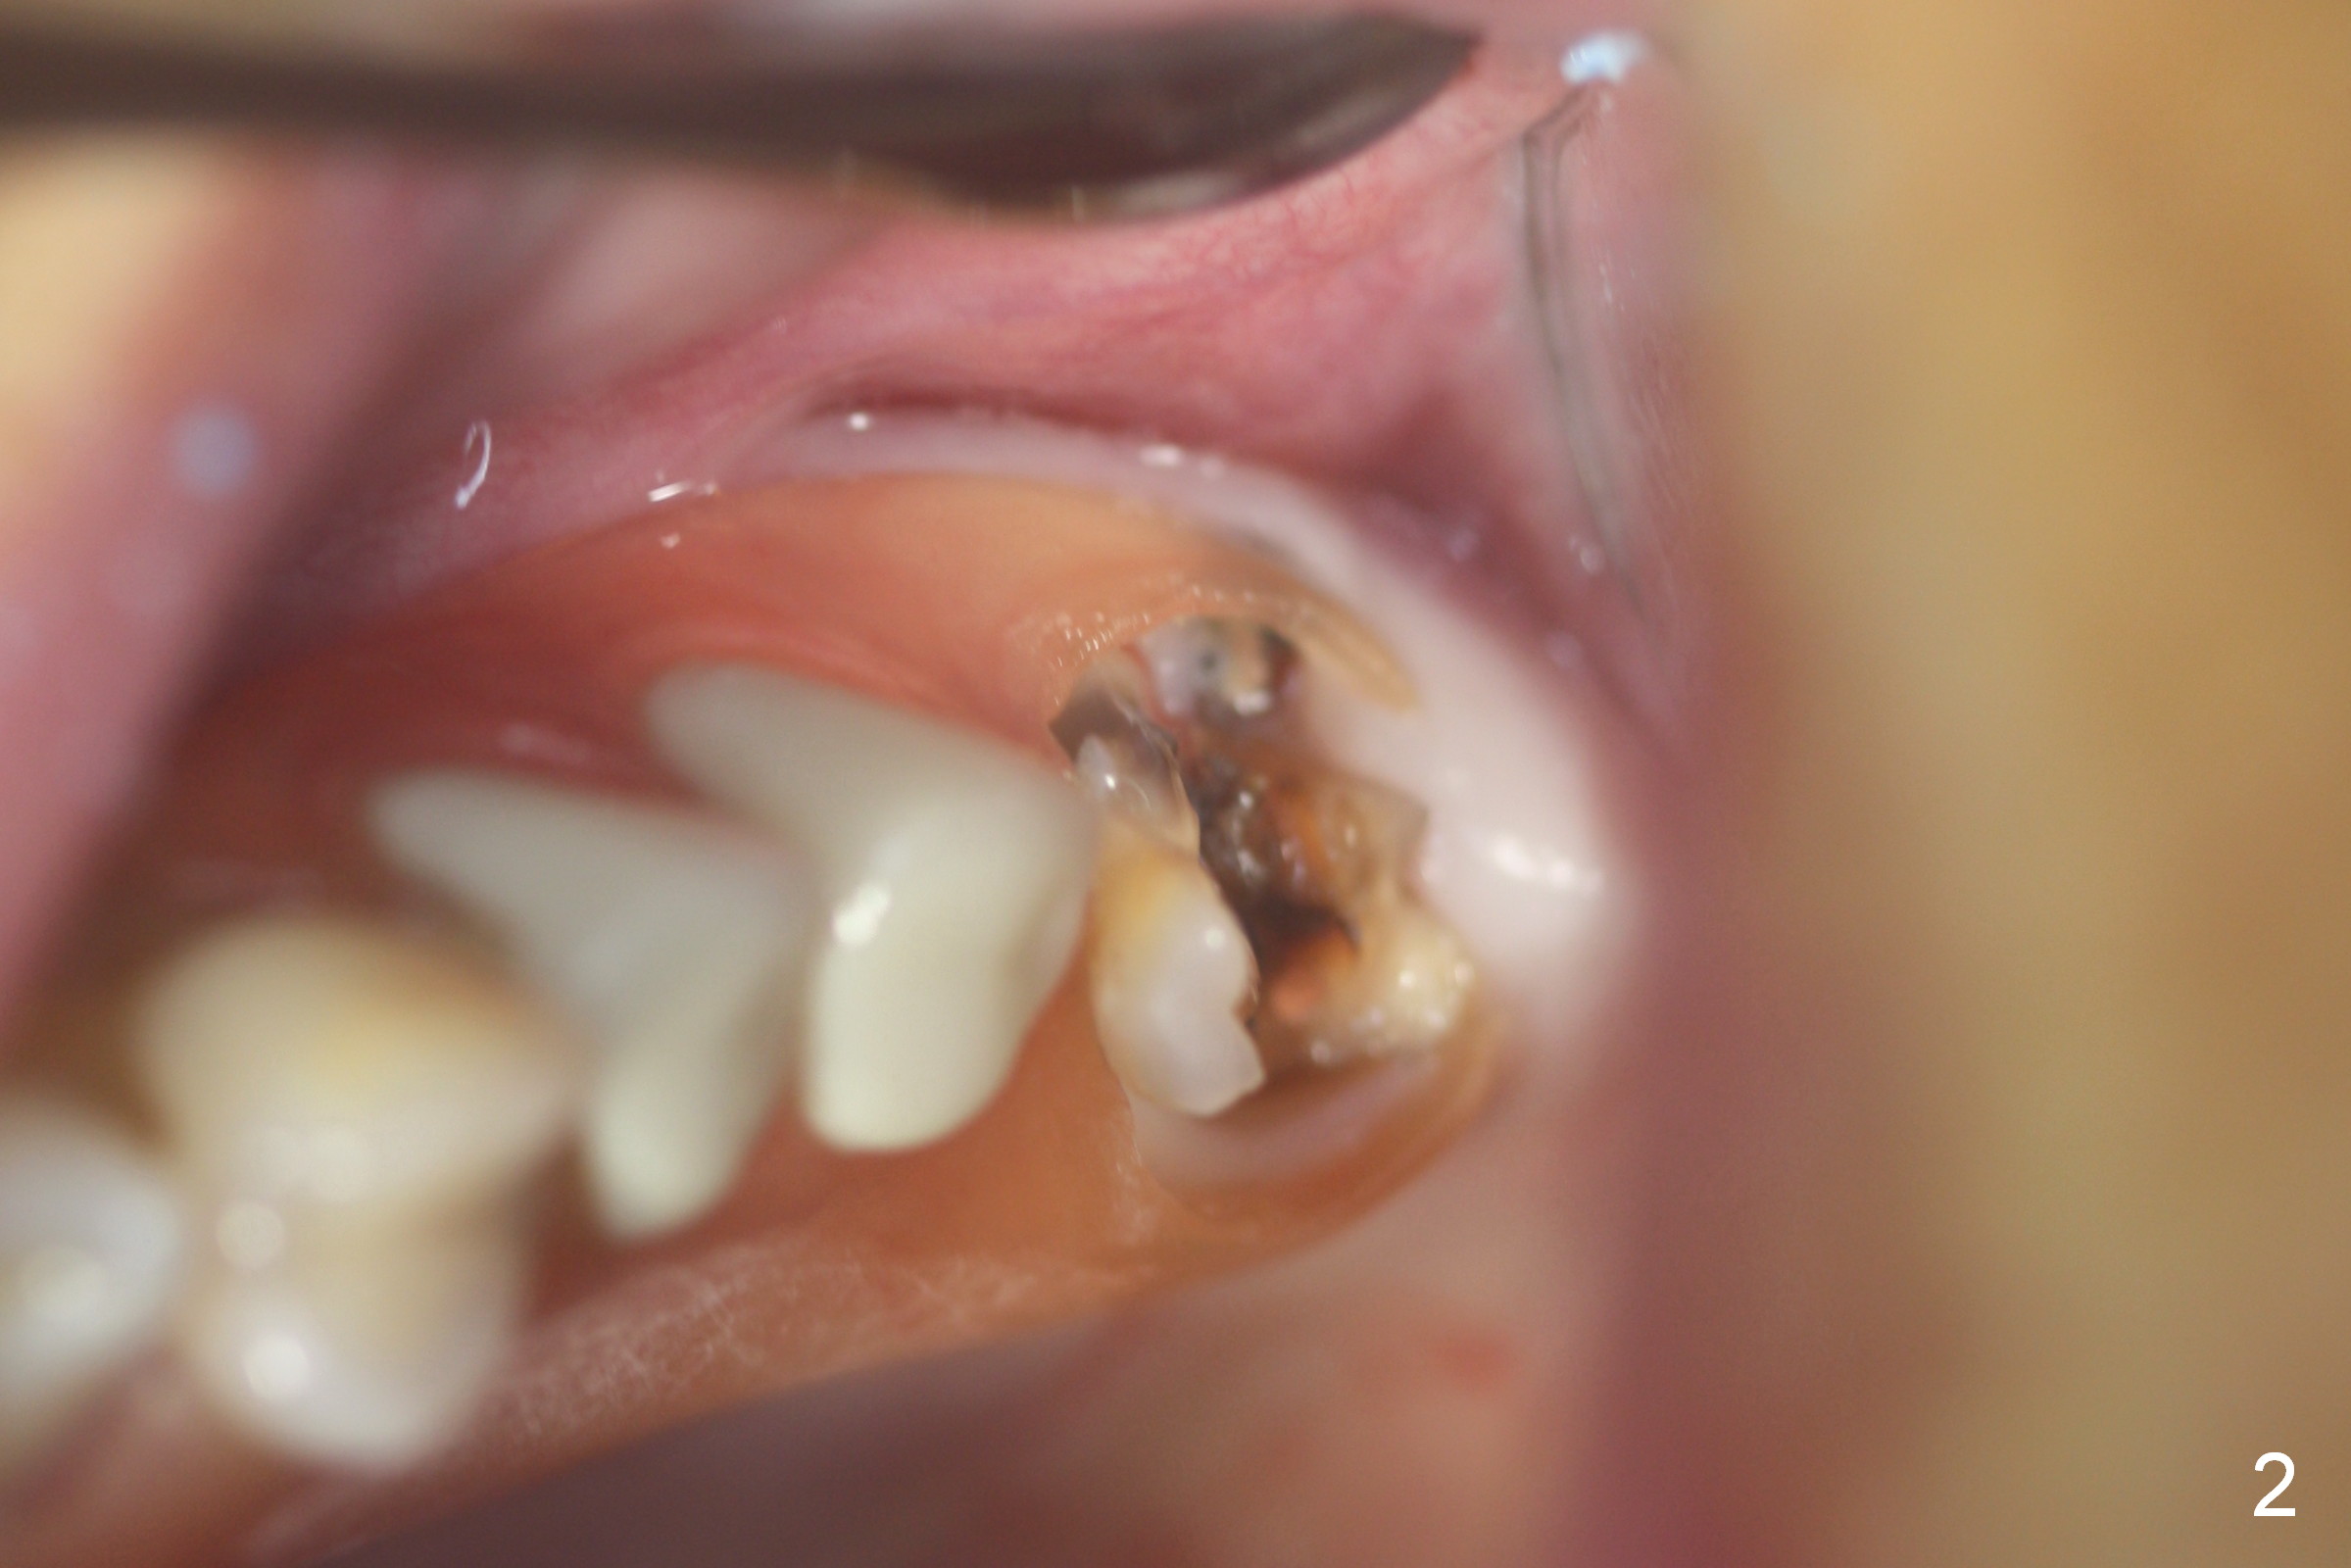

Fig.1,2 show the close relationship of the upper flipper and the residual roots at #15.  Atraumatic extraction using periotomes and surgical sectioning still results in perforation of the mesiobuccal socket (Fig.3 >).  The distobuccal one is shallow, while the septum is small.  It appears that the palatal (Fig.3 P) socket is the most ideal recipient site for the immediate implant and is expanded with Magic Osteotomes until 4.3 mm (Fig.4,5) with the coronal end pushed as buccal as possible.  After placing allograft for sinus lift (Fig.6 >), a 5x11 mm IBS implant is placed with insertion torque ~ 50 Ncm.  A 6x4(3) mm pair abutment is placed, followed by bone graft in the remaining sockets (Fig.6 *) and by Osteogen plug (Fig.7 *).  Finally the socket is sealed by applying acrylic over the abutment (Fig.8).  While the acrylic is setting, the flipper is seated and excess acrylic is removed and pushed away from the flipper (Fig.9).  Advise the patient not to wear the flipper.  If it is being worn, there will be minimal contact between the flipper and the immediate provisional.